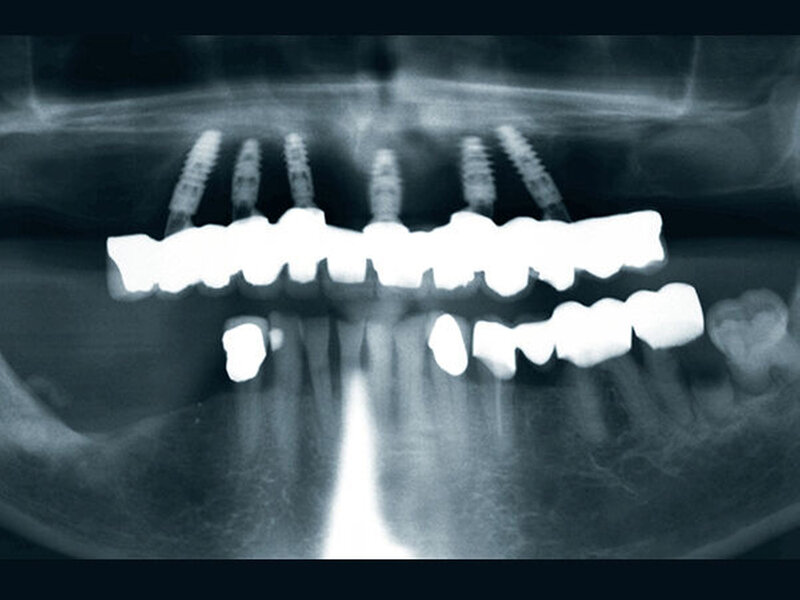

Buhtz: Korrekt, die Voraussetzung ist lediglich die Generierung von DICOM- und STL-Daten, die im Computer exakt übereinandergelegt werden können. Dann erfolgen die Behandlungsplanung wie gewohnt mit ICX-Magellan und die provisorische ‧Versorgung mit dem präfabizierten, chairside hergestellten verklebten PMMA-Provisorium (ICX-‧Smile‧bridge). Seit eineinhalb Jahren arbeiten wir zudem mit dem medentis Fräszentrum Denta5 zusammen.

Buhtz: Wir schicken die Scan-Daten, ein Wax-up und ggf. das Modell mit den Laborimplantaten an das medentis-Fräszentrum und erhalten zwei Tage später die verschraubte Unterkonstruktion. Denta 5 gibt es bereits seit einigen Jahren. Doch erst seit wir einen eigenen Modellscanner haben, stellen wir verschraubte Brücken auf diese Weise her. Jetzt habe ich eine Zahntechnikerin, die damit gut klarkommt. Full-arch-Versorgungen sind bei uns allerdings nicht das Tagesgeschäft, wir machen das vielleicht zehn- bis zwanzigmal pro Jahr. Unsere Patientenklientel ist in der Regel nicht zahnlos.

Buhtz: Egal, wie viele Implantate ich wo setze – am Anfang stehen in meiner Praxis meist eine DVT-Aufnahme und eine 3D-Planung. Ohne Schablone setze ich heute nur noch in absoluten Ausnahmefällen ein Implantat. Die Sicherheit und die gute Planbarkeit reduzieren die Angst der Patienten vor dem Eingriff und erleichtern die Aufklärung. Artefaktarme DVT-Aufnahmen sind natürlich für die Präzision entscheidend.

Die ideal prothetisch ausgerichtete Implantatposition ist der wohl wichtigste Erfolgsfaktor in der Implantologie. Mit ICX-Magellan lässt sich das einfach, schnell und kostengünstig realisieren.